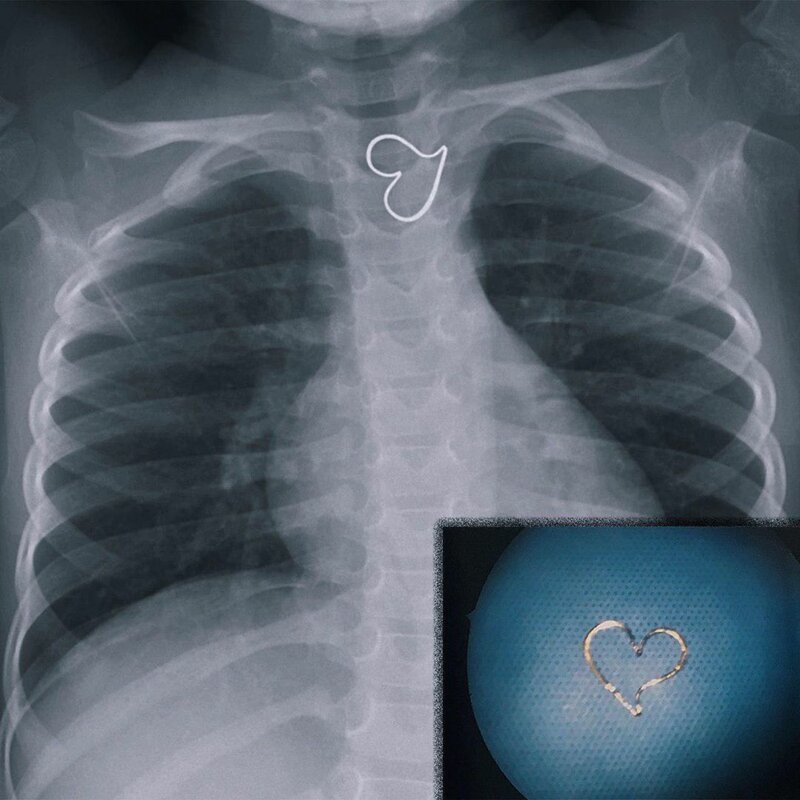

Проглотила кулон